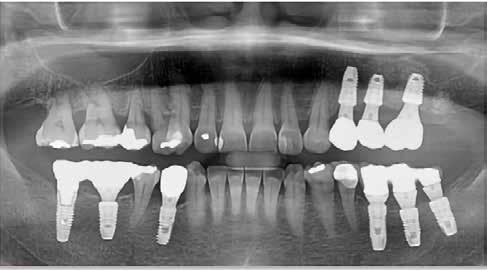

lás vált szükségessé, azt sikertelenségnek vettük. Az implantátumok sikerességi aránya 100%-os volt 18 hónap után (9–10. ábra). A előre legyártott azonnali pótlások protetikai sikerességi aránya 90%-os volt. Két esetben a korona levált a felépítményről az első hat hónap során. Egy összefoglaló elemzésben a szerzők összehasonlították a különböző implantátumbehelyezési és terhelési protokollokat (12). A cikkben az azonnali implantáció és azonnali terhelés 98,4%-os

sikerességi aránnyal szerepel. A hagyományos protokollok, ahol a késői implantációt hagyományos késői terhelés követi, a sikerességi arány 97,7%. Meg kell jegyeznünk azonban, hogy a szisztematikus áttekintésbe bevont cikkek között a bizonyítékok szintjében néha lényeges különbségek voltak, amikor az egyes protokollokat összehasonlították. Az azonnali implantáció adatai klinikailag dokumentált adatokra korlátozódtak.

9. ábra: Különböző stádiumnál készített röntgenfelvételek.

10. ábra: Kontroll 18 hónappal később.